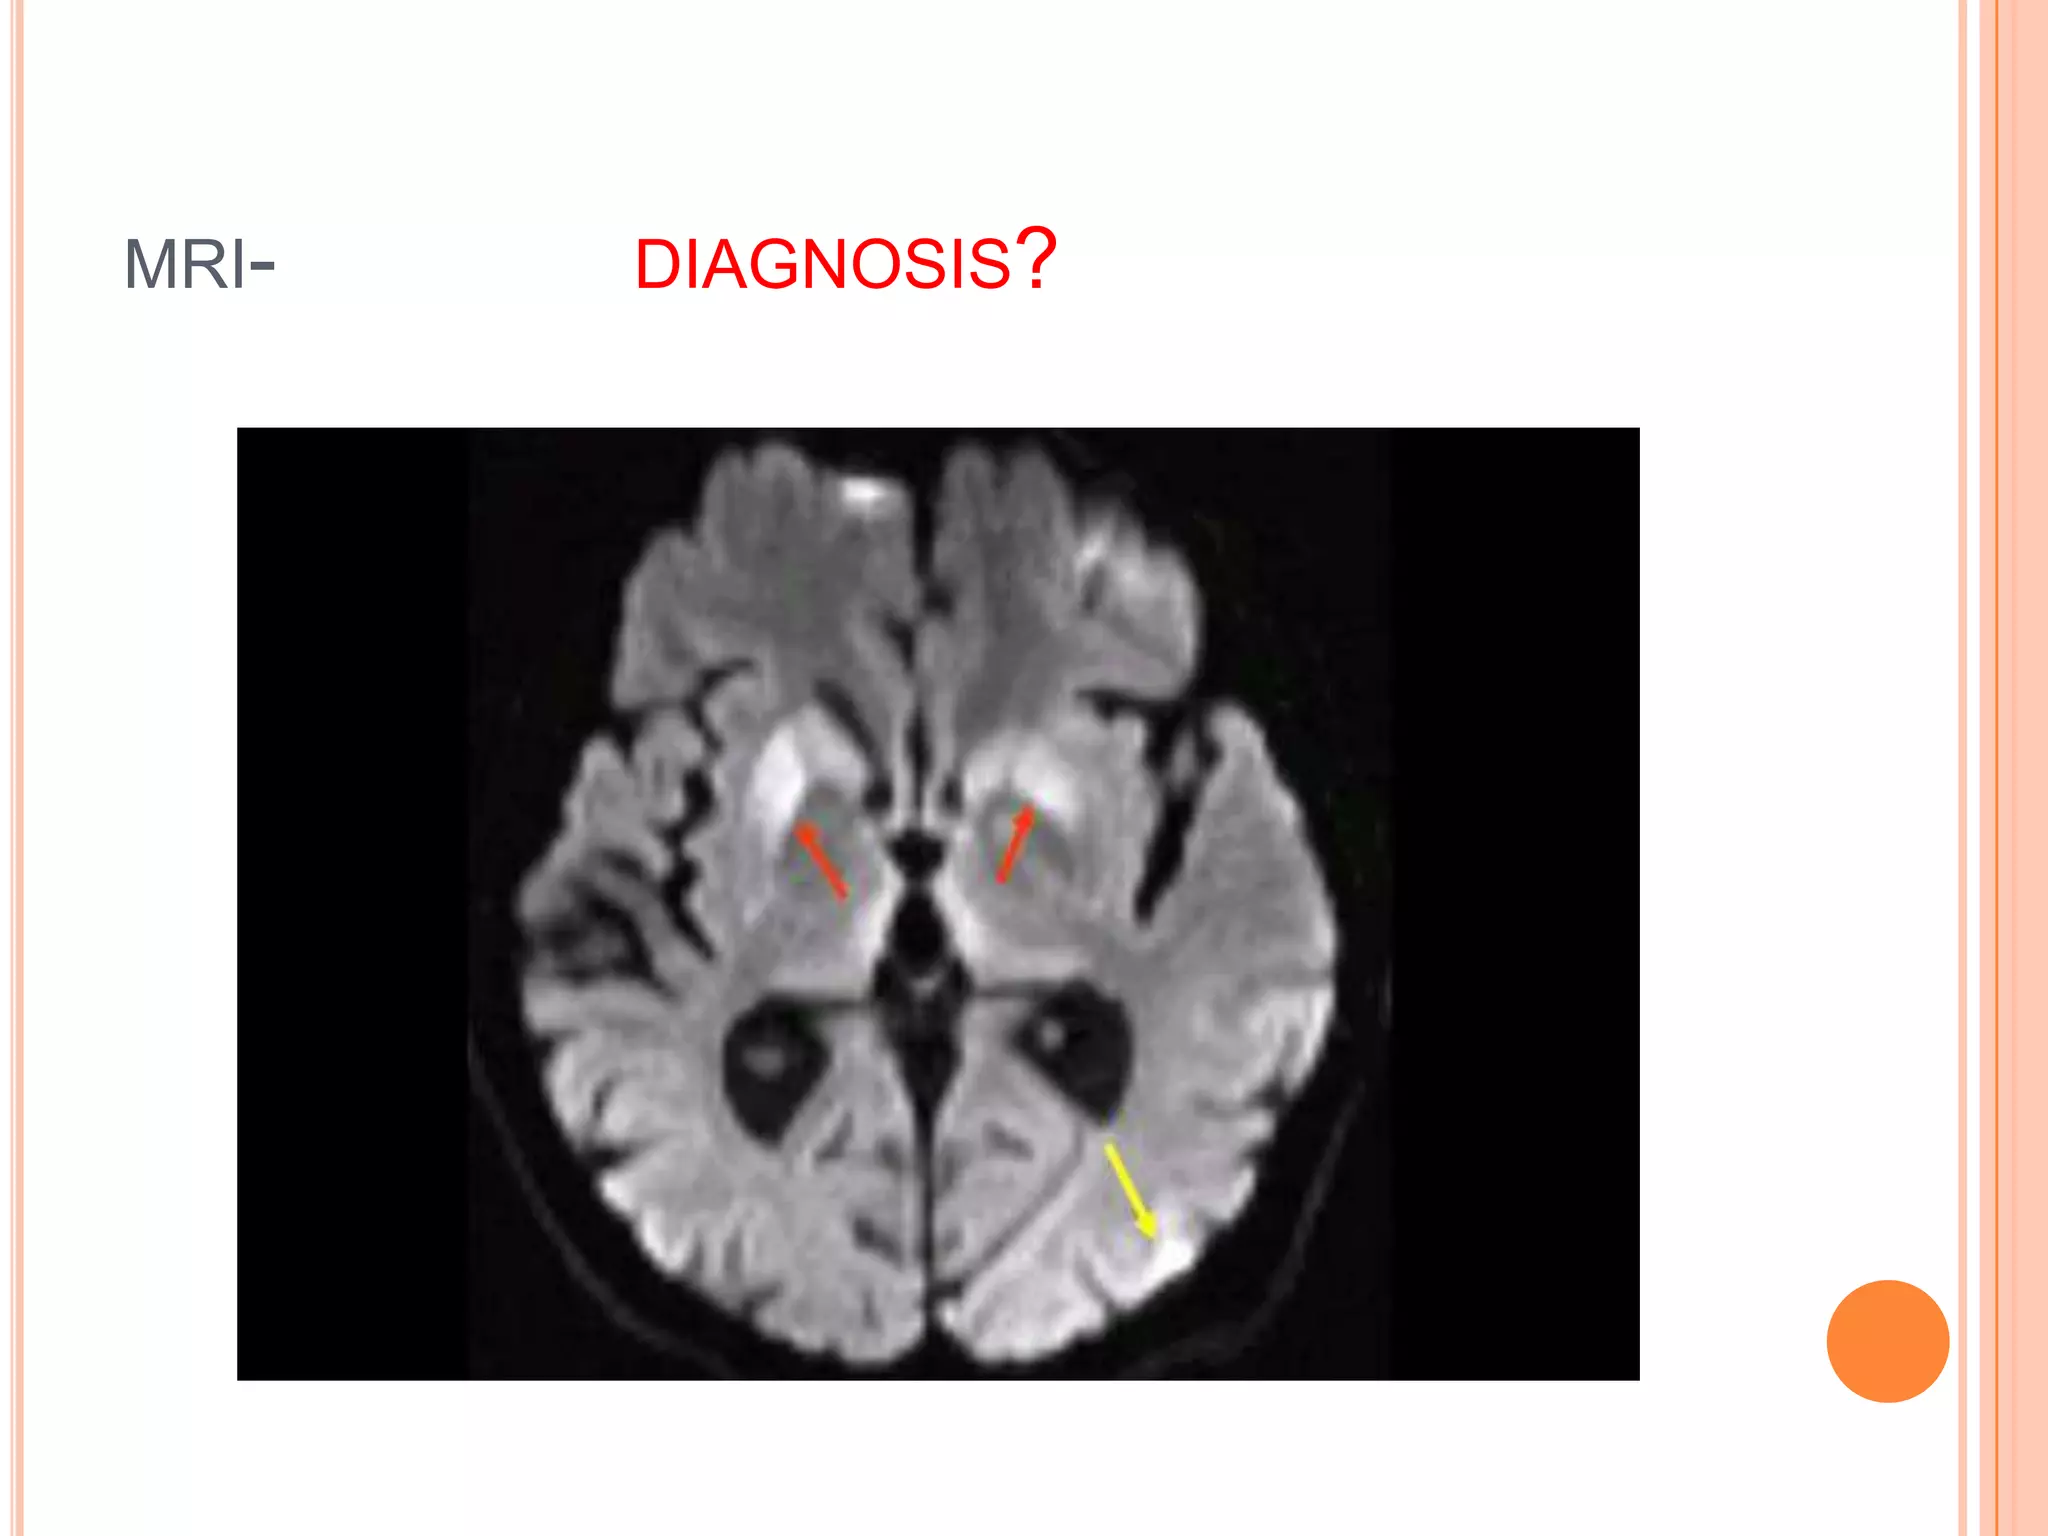

MRI- DIAGNOSIS?

CRUETZFELDT-JAKOB SYNDROME(CJD)

 MRI- basal gangla abnormalities